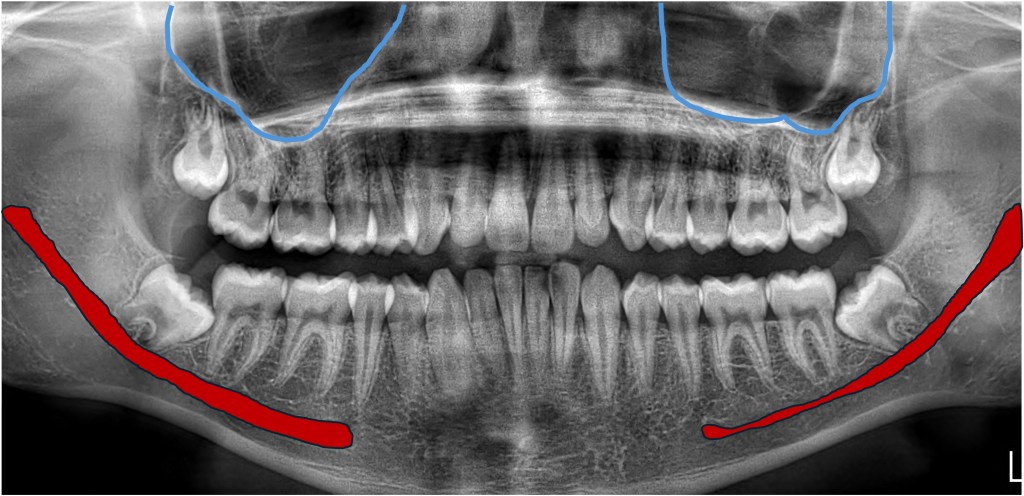

The force that pushes a tooth into the mouth is the formation of the root, which acts like a rocket to propel it, ideally, into the perfect position. The crazy thing is, the longer the roots get, the closer they get to important structures like the sinuses (near top wisdom teeth) and a nerve that gives the feeling to your lower lip and chin (bottom ones). If those roots get super close, touch, or “wrap around” those structures, there is increased risk of damage.

Fortunately injuries to these things are rare, but when they happen, they can be a problem. Here’s what we see on basic x-rays: